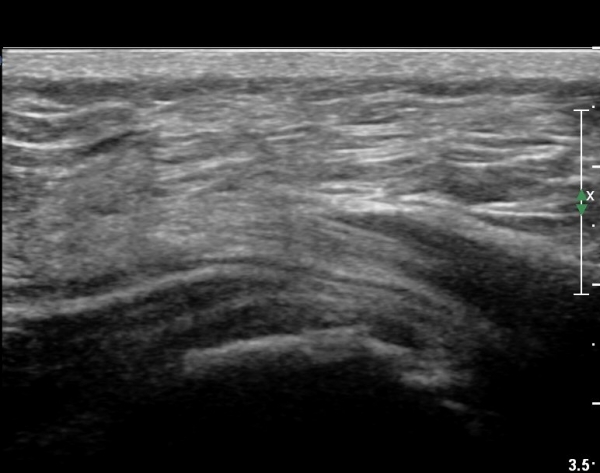

ÃÊÀ½ÆÄ °Ë»ç

Á¡¾×³¶³» ÁÖ»çÄ¡·á¿Í ¼®È¸ÀÇ ÁÖ»ç¹Ù´Ã ÀÚ±Ø(needling)